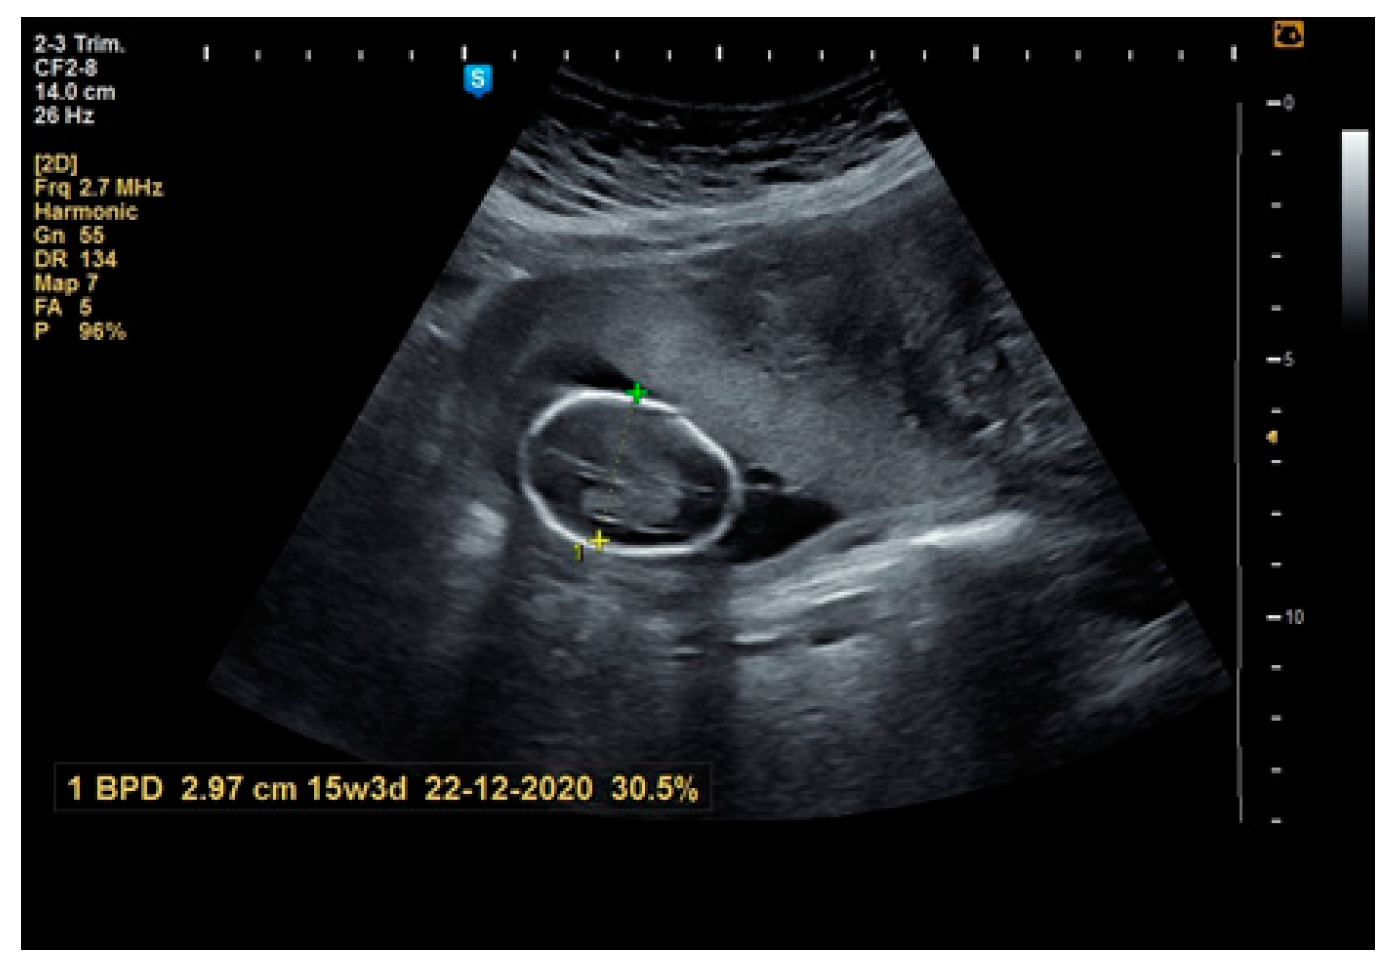

2. Materials and Methods

3. Results